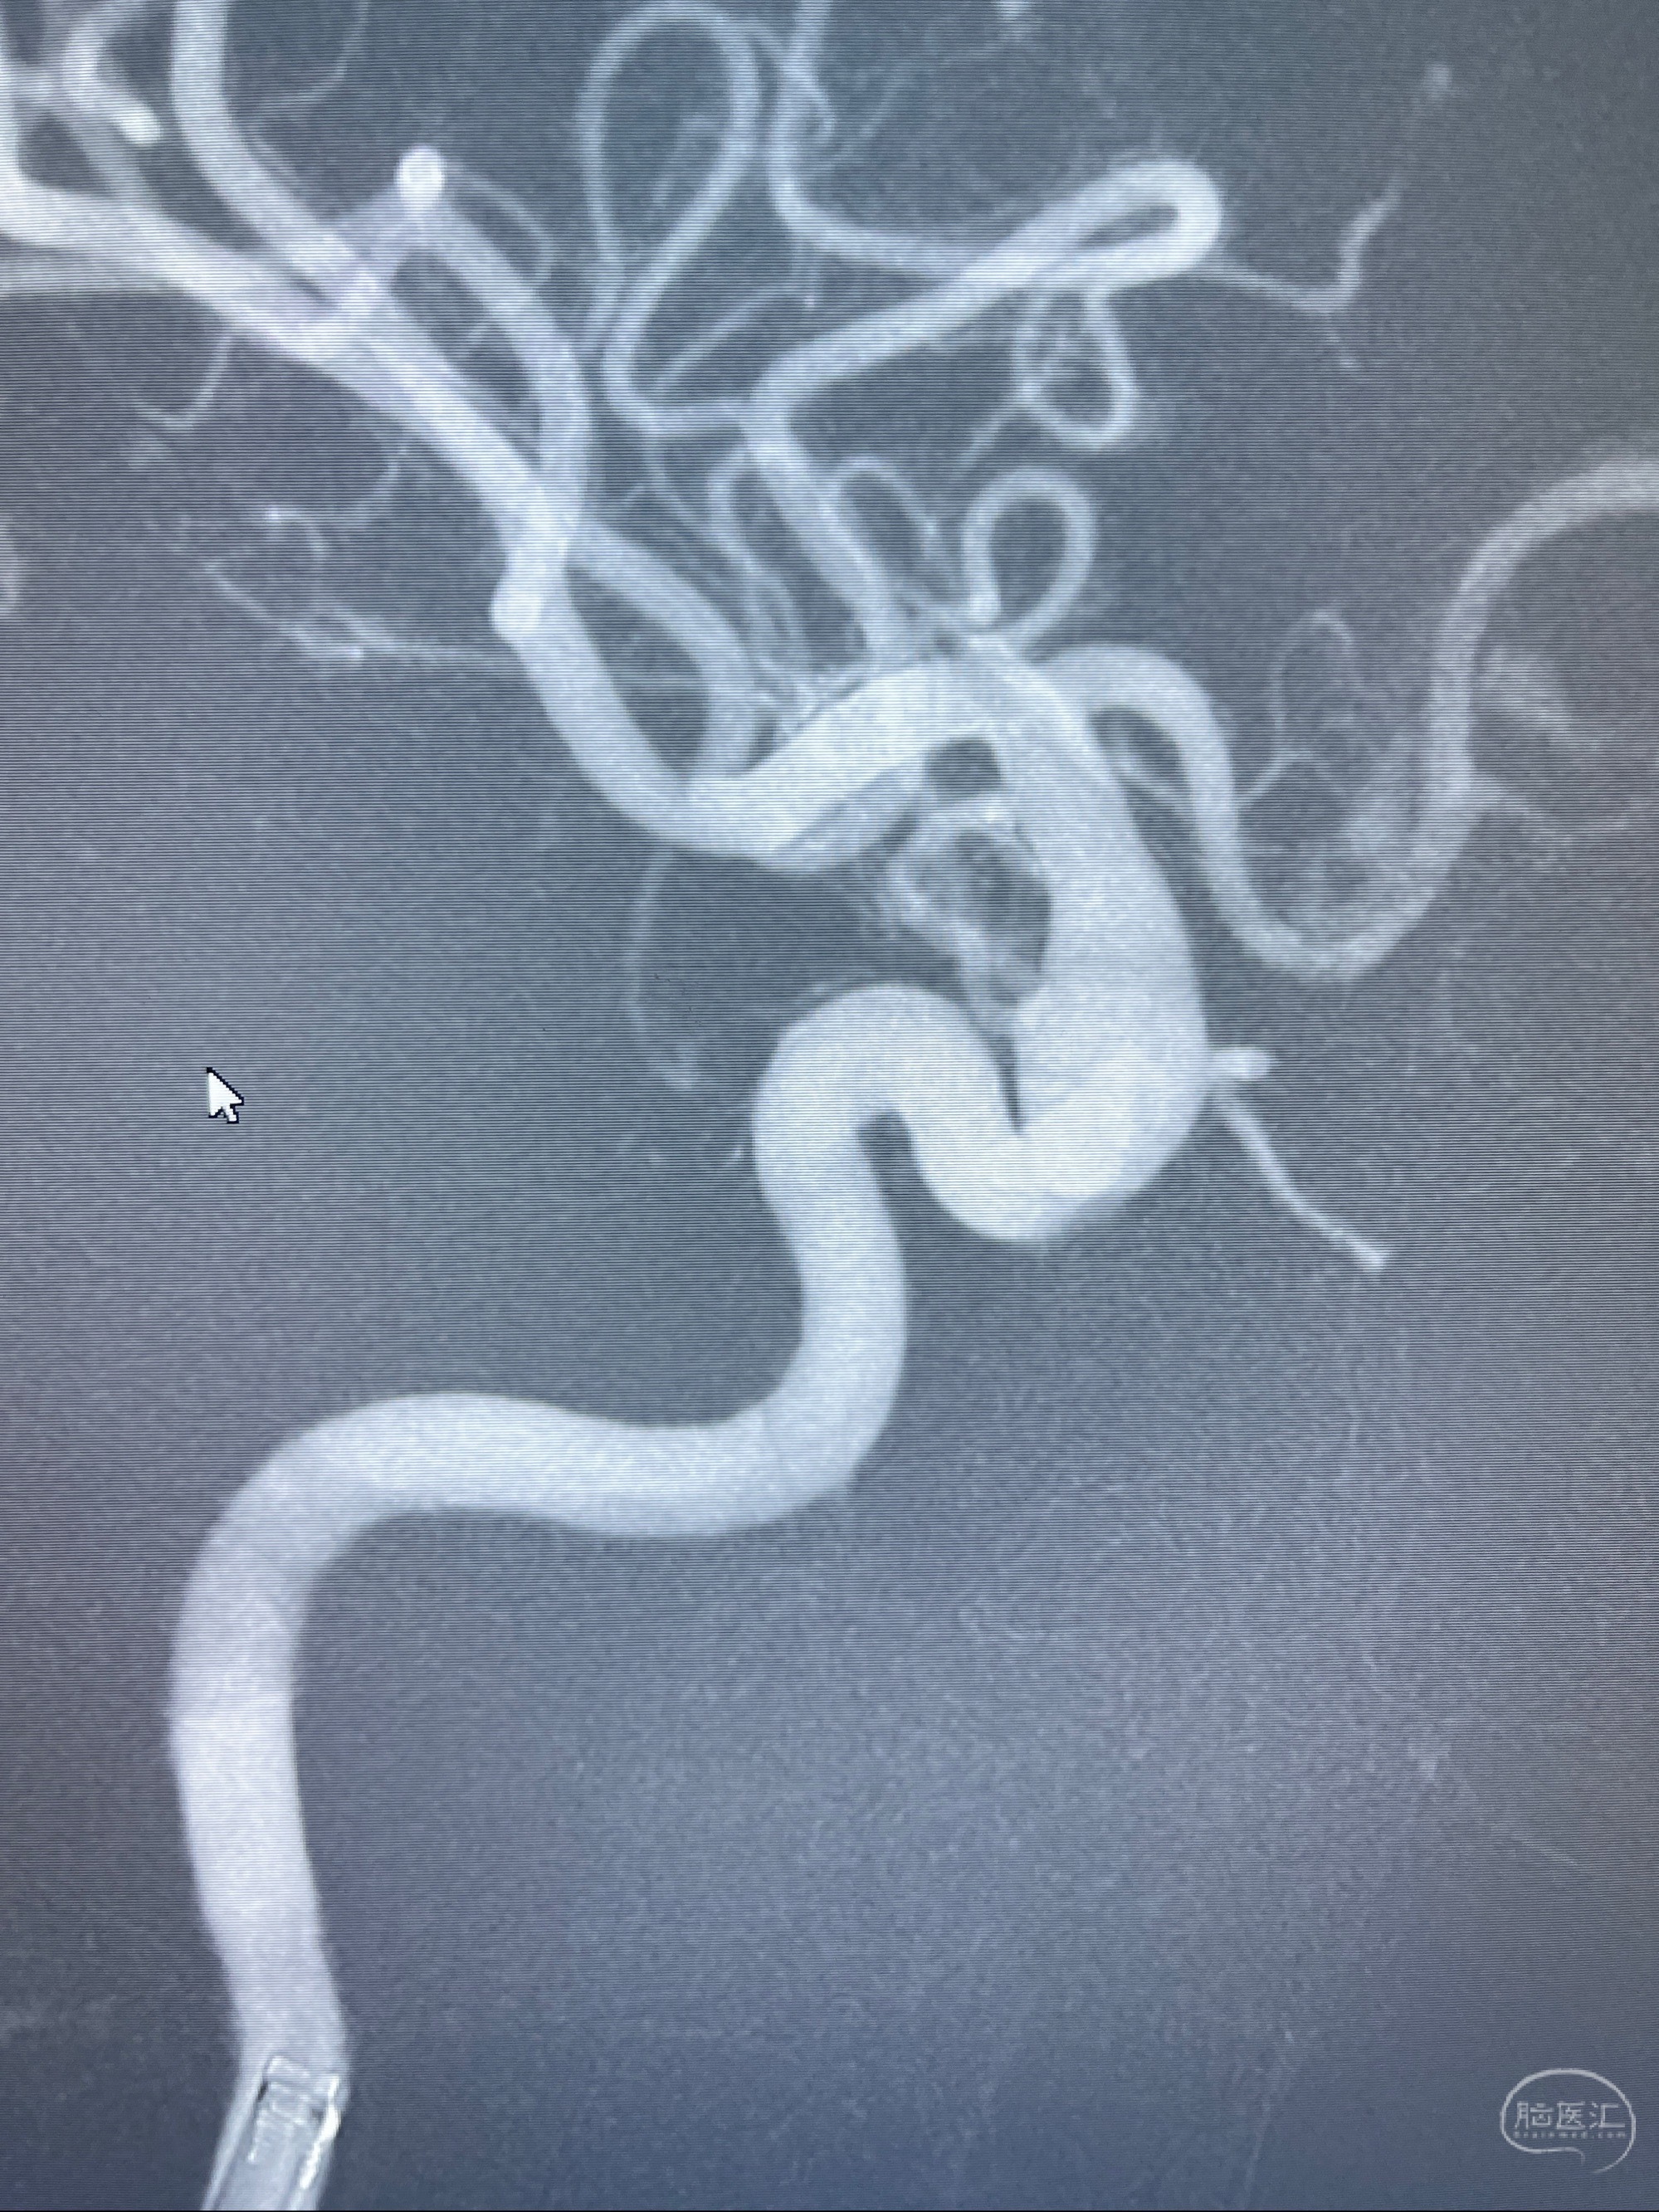

2023.07.25 泰州市人民医院查头颅CTA提示右侧C6段瘤样突起,建议DSA检查;

CTA示:右侧颈内动脉C6段见指向下方的突起,余左侧颈内动脉、双侧椎动脉、大脑前动脉、大脑中动脉、大脑后动脉及基底动脉走形正常,未见明显扩张及狭窄,局部未见明显瘤样扩张。

2023-07-27全脑血管造影:双侧颈内动脉眼动脉段动脉瘤,右侧较大